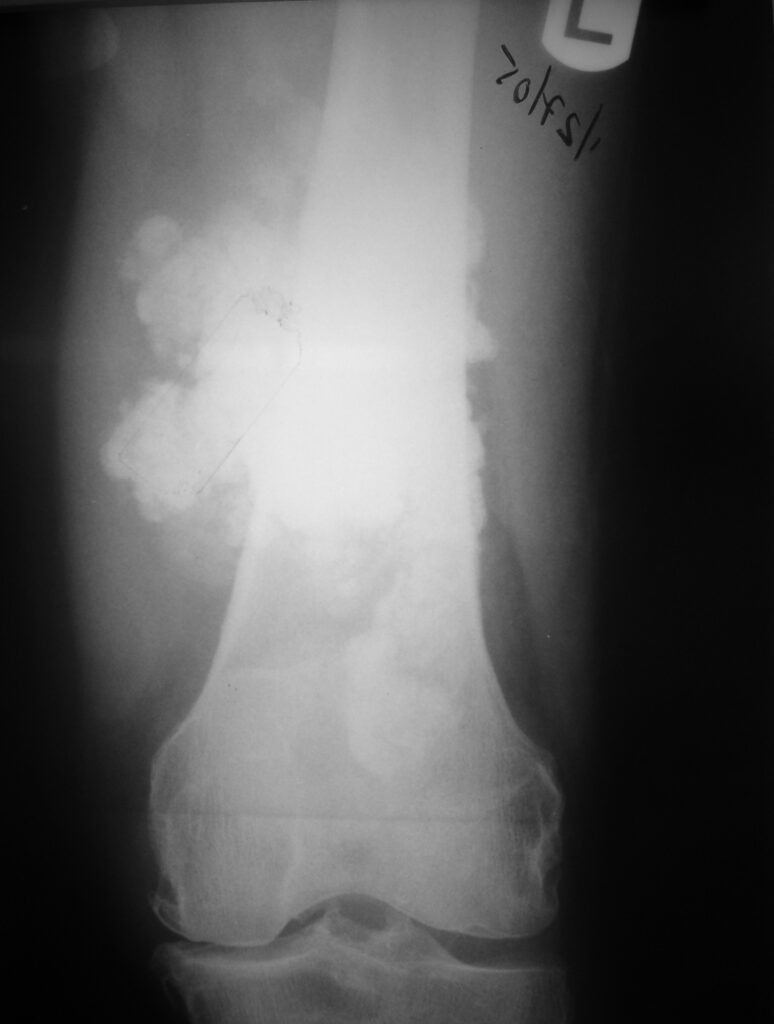

On radiographs, extraskeletal osteosarcomas show a mass with soft tissue density and variable amounts of mineralization best visualize on an Xray or CT scan, which may appear as a dense, cloudlike area (Fig. 1-3). A well circumscribe heterogeneous mass, Isointense to muscle on T1-weighted images and isointense to mildly hyperintense on T2-weighted images (Fig. 4-7). Mineralized areas will be dark on T1 and T2 weighted images.

Fig. 1 & 2: Plain x-rays of the distal femur showing an extraskeletal osteosarcoma. AP (Fig. 1) and Lateral (Fig. 2) views show a soft tissue density with intense mineralization in the posterior thigh. Mass is not originating from the bone.